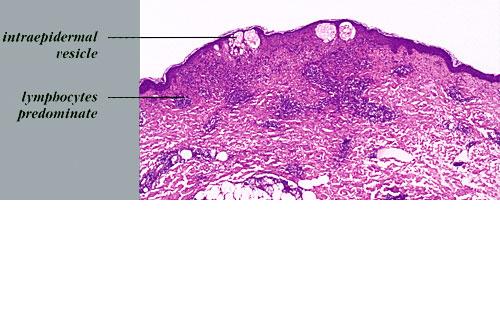

Herpes simplex = العقبول البسيط